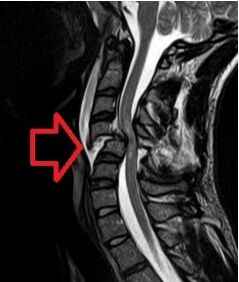

45.一位52歲男性綁安全帶坐在駕駛座時,在高速公路發生追撞車禍,在急診室發現十二指腸破裂緊急接受手術,隔日在病房抱怨頸部痠痛且合併手腳麻痺現象,頸部核磁共振影像如下,下列敘述何者正確? (A)影像顯示為頸椎第四節滑脫(spondylolisthesis),導致第四脊髓壓迫損傷 (B)肌力評估發現上肢力氣比下肢差,感覺有保留,所以認為是前髓症候群 (C)患者在手術後口含氣管內管戴頸圈搖高30度坐起時會感到頭暈,血壓下降至76/54 mmHg表示可能有 姿勢性低血壓 (D)用呼吸器時血氧偵測數值為95%,所以不需要呼吸訓練